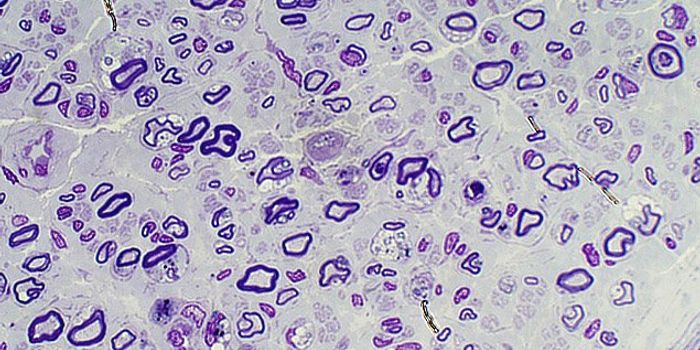

MAR 03, 2016Cell & Molecular BiologyFor the first time, scientists have turned skin cells into cancer-hunting stem cells that destroy brain tumors known as ...